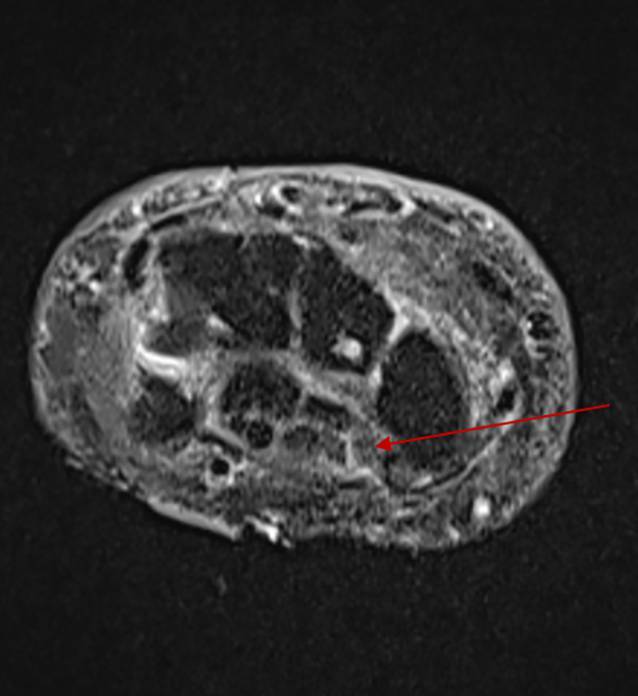

Immune checkpoint inhibitors (ICIs) are successfully used in multiple malignant diseases. Their spectrum of adverse effects includes dermatological, endocrinological, gastrointestinal, and hepatic toxicities, as well as rare neurological side effects affecting the central nervous system and more frequently the peripheral nervous system. Pre-existing neurological disorders may deteriorate. Bilateral carpal tunnel syndrome (CTS) rarely occurs. In the present case, an 83-year-old patient with stage IIIC malignant melanoma (MM) developed pain, swelling, and paresthesia in both hands after five adjuvant therapy cycles with pembrolizumab 200 mg. Following the diagnosis of bilateral CTS, pulse therapy with prednisolone was initiated and subsequently reduced to a maintenance dose of 20 mg orally. Despite the necessary escalation of ICI therapy to ipilimumab/nivolumab due to MM progression, CTS improved under concomitant prednisolone therapy and physiotherapy.

Abstract Image